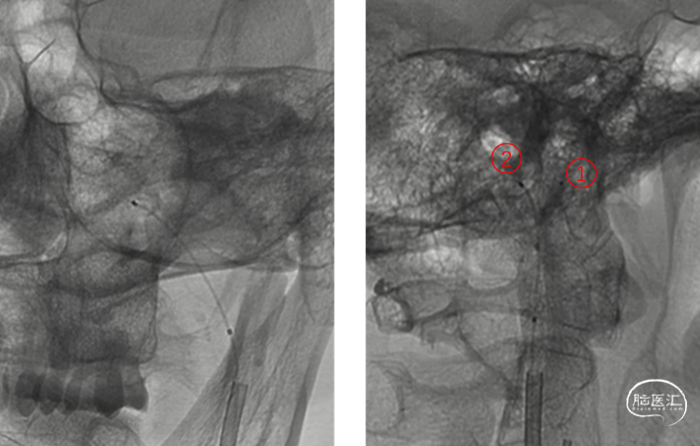

e、再在Syn-14微导丝导引下先将Echelon-10 微导管置于左侧髁前汇内(①为Marathon,②为Echelon-10)

f、 经Echelon-10送入JasperSS 3mm*8cm弹簧圈,推送顺利,在髁前汇内分布均匀,造影见瘘样染色改变不明显

g、再次送入JasperSS 3mm*8cm弹簧圈,输送顺利,复查造影可见向岩下窦反流消失。

h、用DMSO冲洗Marathon微导管后,将Onyx胶缓慢注入,透视下见Onyx胶弥散至动静脉瘘处。

通过静脉端进行栓塞,先通过弹簧圈(红圈)在髁前汇内成篮,一方面可以部分阻挡血流,更主要的是为后续的Onyx胶(紫点)搭建一个“金属笼”,防止液体栓塞胶向静脉端过度反流,而主要向瘘口方向弥散,从而达到完全栓塞;这样弹簧圈的栓塞率不需要很高,减少其对周围舌下神经的压迫,避免出现持续性的舌下神经损伤。